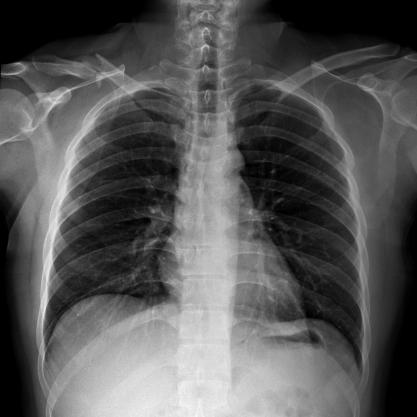

滿足不同身高的受檢者快速地進行胸片的靜態(tài)及動態(tài)檢查,適合大規(guī)模體檢。

● 可快速選擇、預設所需要的視野,節(jié)約擺位時間;

● 根據(jù)拍攝需求或技師使用習慣一鍵切換光束范圍;

● 可根據(jù)不同的體位協(xié)議,自動調(diào)整光束大小。